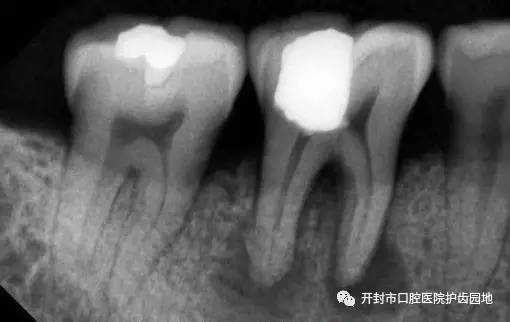

根管治疗 是牙髓病和根尖周病的国际上最常用的有效治疗方法。根管治疗术的原理是通过机械和化学方法去除根管内的大部分感染物,并通过充填根管、封闭冠部,防止发生根尖周病变或促进已经发生的根尖周病变的愈合。今天我们就来了解一下牙齿根管治疗的全过程。

拍X射线照片,确定患处结构和手术方案。 施以局部麻醉。 钻开牙齿,去除腐坏的牙体组织。 打开牙髓腔,取出牙髓组织,并预备成形根管。 用消毒液(例如氯酸钠溶液)冲洗根管内部后,再用专门的材料充填根管,保证长期处于无菌状态。 填补牙齿的钻洞,或安装牙冠。 最后我们来看一看根管治疗后的X射线照片,是不是很完美。 牙体牙髓科科 牙体牙髓科是我市口腔医院主要临床科室之一,开封市医学重点专科。拥有超声综合治疗仪、镍钛根管预备和热牙胶根管充填器械、根管长度测量仪、牙髓活力测试仪等技术设备,牙体充填修复材料应用与国内前沿同步。精于龋病、牙髓病和根尖周病的诊治,年轻恒牙根尖诱导术、牙本质过敏症、牙外伤的诊治,前牙无髓变色牙的内漂白治疗。开展的牙髓病无痛治疗术、ProTaper预备根管和热牙胶充填术等。 牙体牙髓病科 张运祥 文中图片来源于网络 张运祥 市口腔医院牙体牙髓病科主任,主治医师,郑大口腔医学院学士学位。擅长龋病、牙髓病、根尖周病等治疗,熟练开展国际先进的“镍钛机动根管预备”、“热牙胶三维根管充填”等技术。